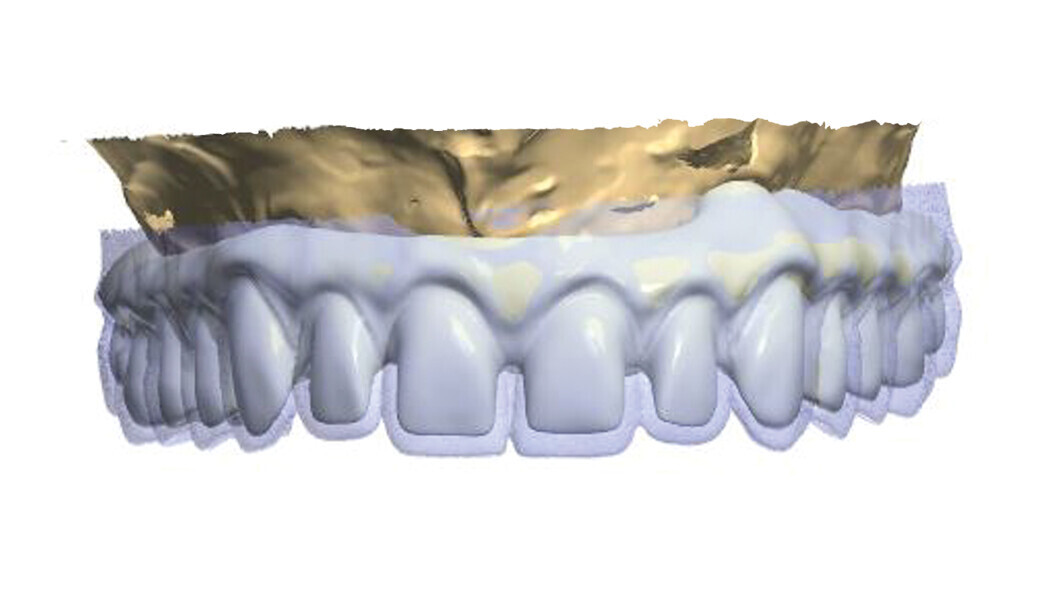

Fig. 2: Design of the construction with the transparency mode on.